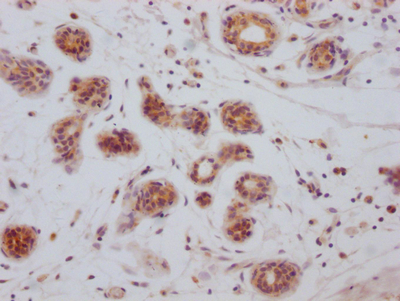

IHC image of CSB-RA247982A0HU diluted at 1:100 and staining in paraffin-embedded human breast cancer performed on a Leica BondTM system. After dewaxing and hydration, antigen retrieval was mediated by high pressure in a citrate buffer (pH 6.0). Section was blocked with 10% normal goat serum 30min at RT. Then primary antibody (1% BSA) was incubated at 4℃ overnight. The primary is detected by a Goat anti-rabbit IgG polymer labeled by HRP and visualized using 0.05% DAB.